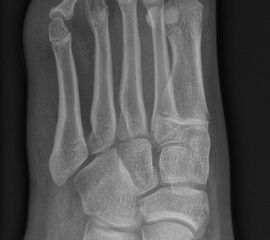

Abb. 2 a-c: offene Wachstumsfugen MT I Basis und Zehen (a), teilweise geöffnete Wachstumsfugen (b) und geschlossene Wachstumsfugen (c).

Die erforderlichen Osteotomien sind daher dem Fugenverlauf anzupassen, diese sind unbedingt zu respektieren. Wird eine Wachstumsfuge versehentlich mit der Fräse verletzt, kann durch partiellen oder kompletten Fugenverschluss ein Fehlwachstum provoziert werden. Achsabweichungen oder ein Wachstumstopp der betroffenen Region können die Folge sein. Offene Wachstumsfugen begrenzen die Osteotomieausrichtung besonders im Bereich des dorsalen Calcaneus, der Metatarsale I Basis und der IV. oder V. Zehe im End- und Mittelglied.

Zusätzlich schränken Wachstumsfugen die Wahl der Osteosynthese ein. Eine die Fuge kreuzende Osteosynthese ist ausschließlich mit Kirschner-Drähten möglich (Abb. 3).